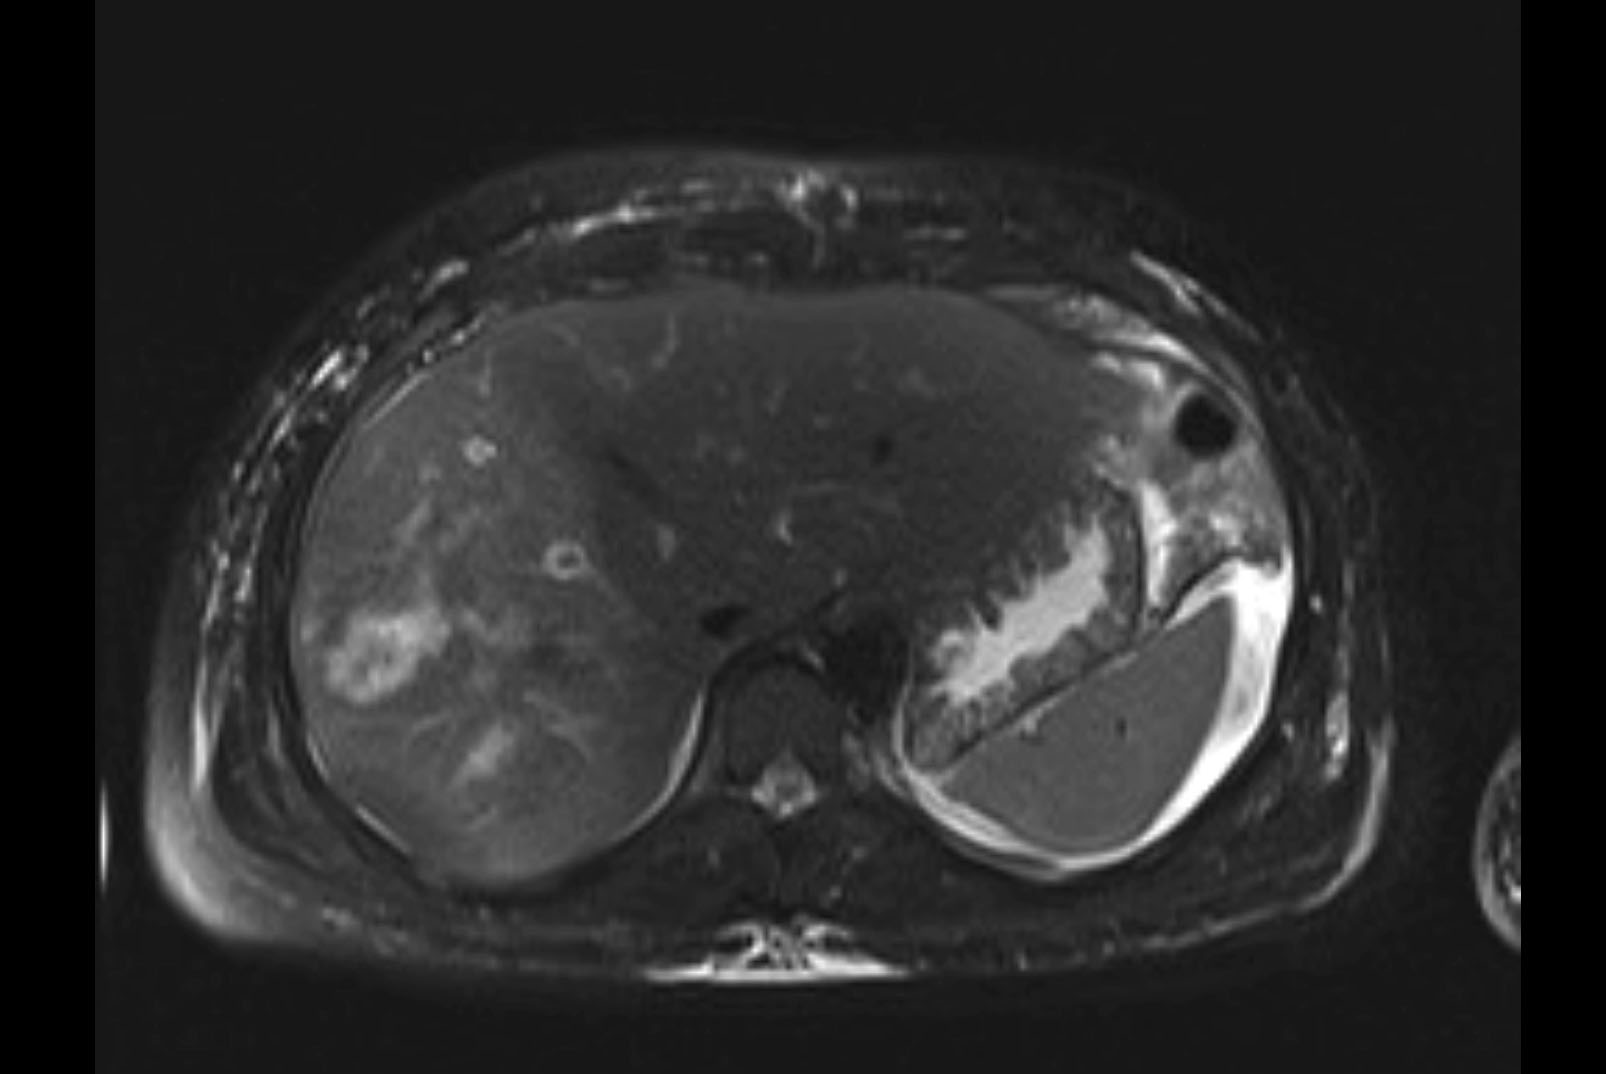

Imaging Analysis

Look through the patient's CT scan to identify any areas of concern for the necessary procedure.

MRI T1

MRI T2

Based on initial findings, which issue(s) would you be most concerned about?